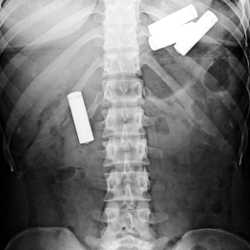

Данные симптомы распространены при кишечных инфекциях, перитоните. Для исключения варианта проглатывания батарейки проведите диагностику с помощью рентгена. Вспомните и сообщите врачу, когда элемент питания попал в организм. Это поможет точнее предположить место нахождения инородного предмета.